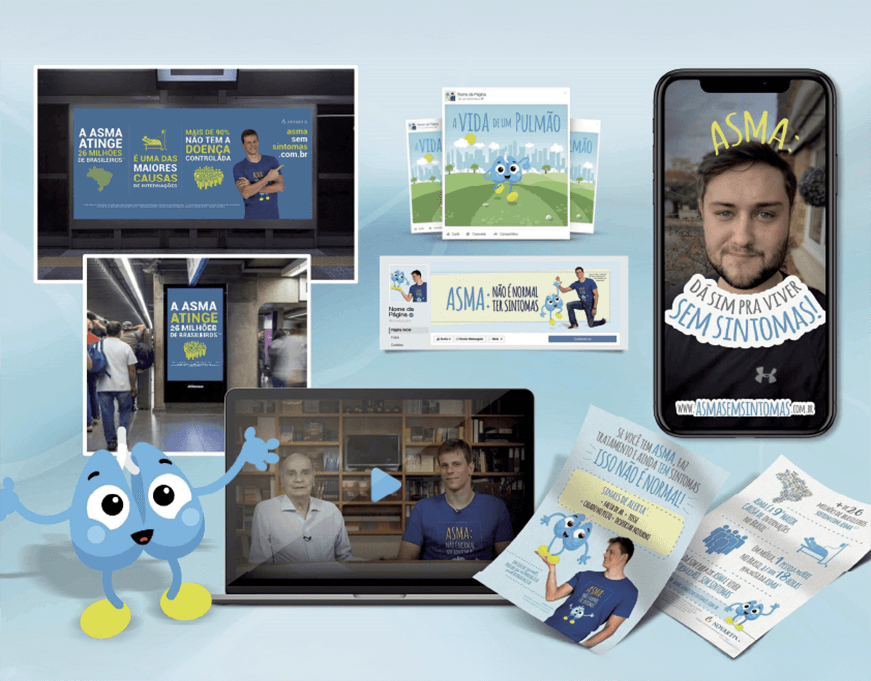

Publicidade

Focados no mercado B2C, atuamos na criação de marcas e campanhas on e off.

Anúncios

Vídeos

Materiais gráficos

Out of Home